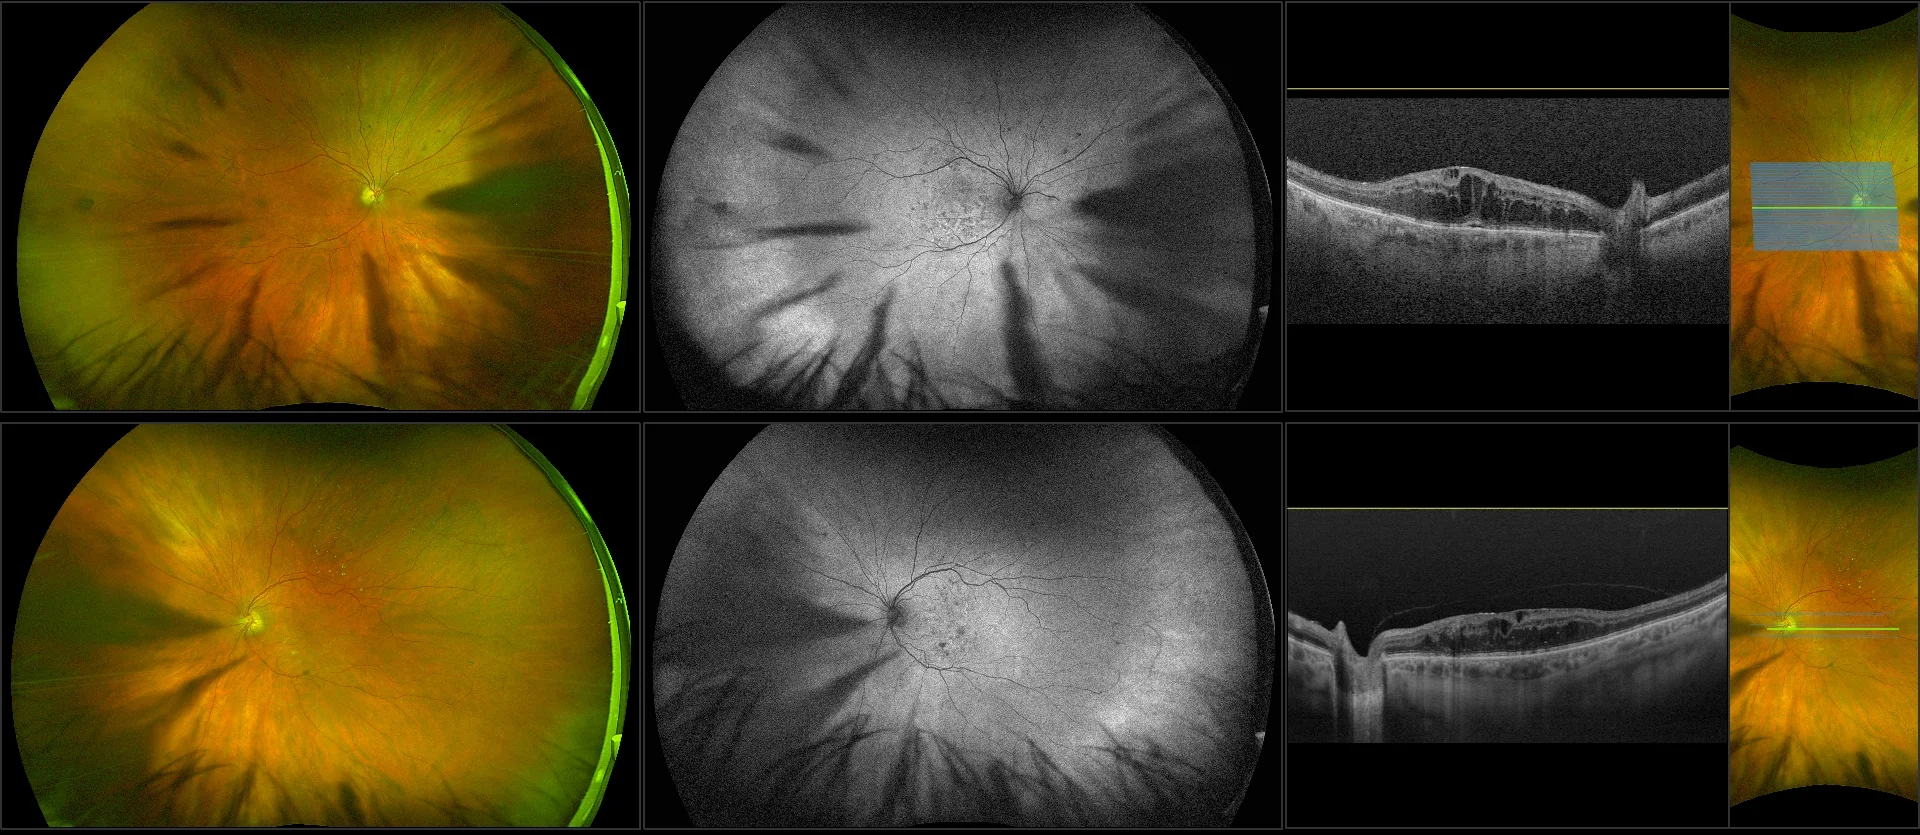

California - Diabetic Macular Edema with Ozurdex Implant, RG, AF

Diabetic macular edema (DME) is the accumulation of excess fluid in the extracellular space within the retina in the macular area